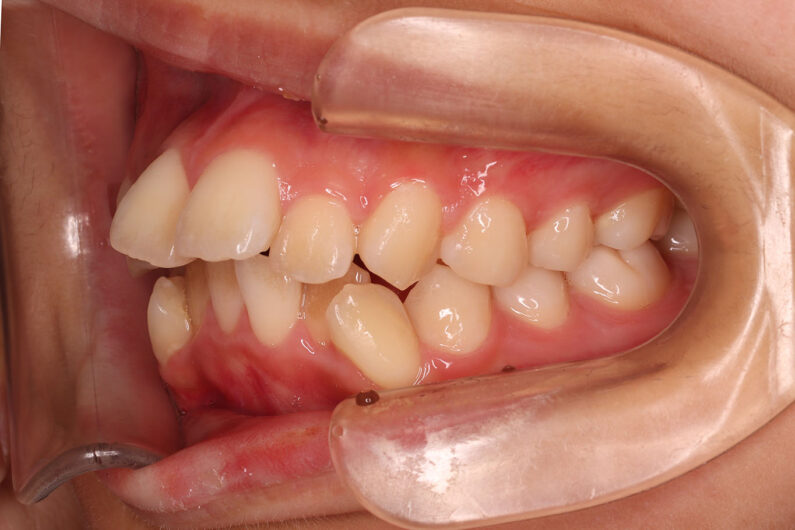

他院から紹介の患者さんです。 前歯、下の歯のガタツキをきれいにしたいということで治療を決断されました。

上顎前歯6mm、下顎前歯2.5mmの前突の状態で、口唇も前突しています。 小臼歯抜歯したスペースを使い、叢生(がたつき)と前突した前歯の後退を目標にしました。 この方も希望により、アンカースクリューは使用せず、通常の顎間ゴムで対処してもらいました。